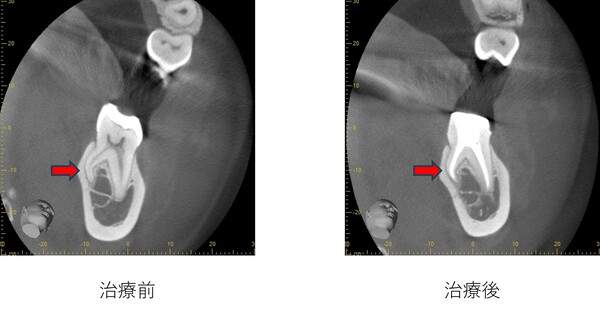

左側の根の先が大きく曲がっています。この場合、ステンレススチールファイルの使用のみで綺麗に治療することは困難です。

Ni-Ti ロータリーファイルを使用することで、大きく湾曲した先まで綺麗に追うことが可能となります。